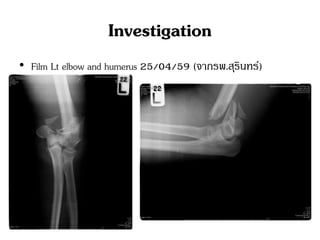

Investigation

• Film Lt elbow and humerus 25/04/59 (จากรพ.สุรินทร์)